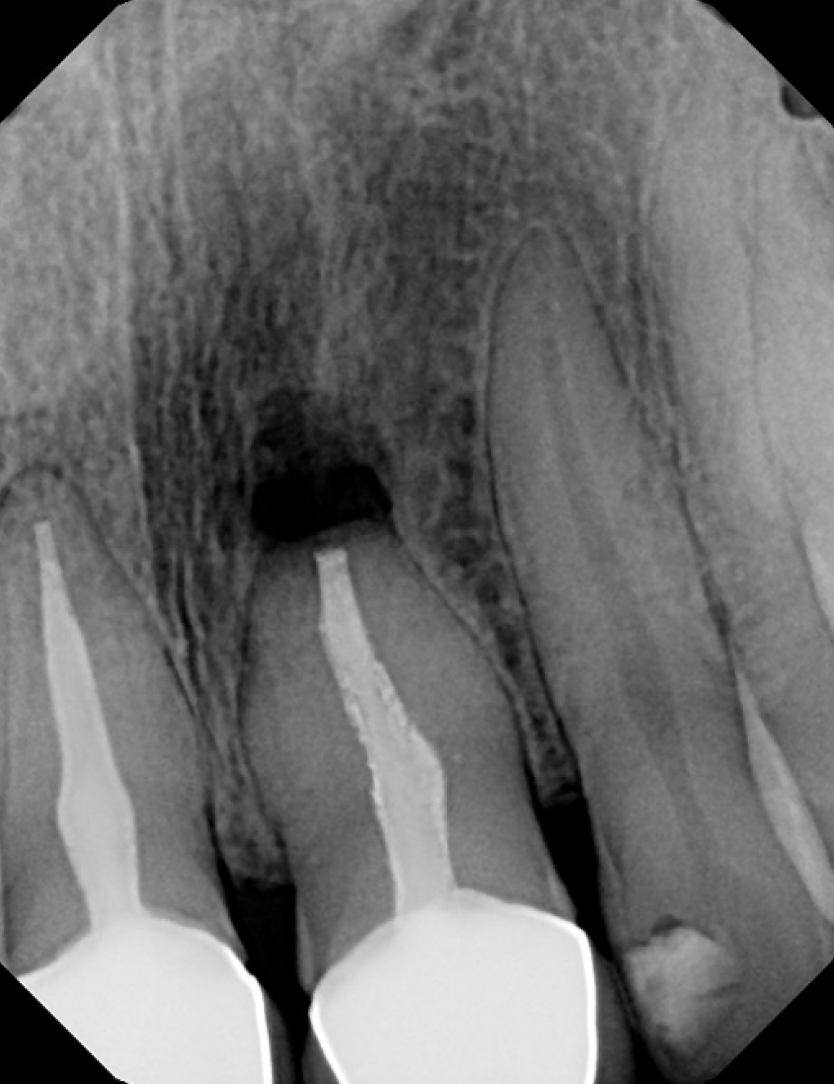

#7 NS-RCT (with SI retrieval)

Dx: Previously Initiated with CAA